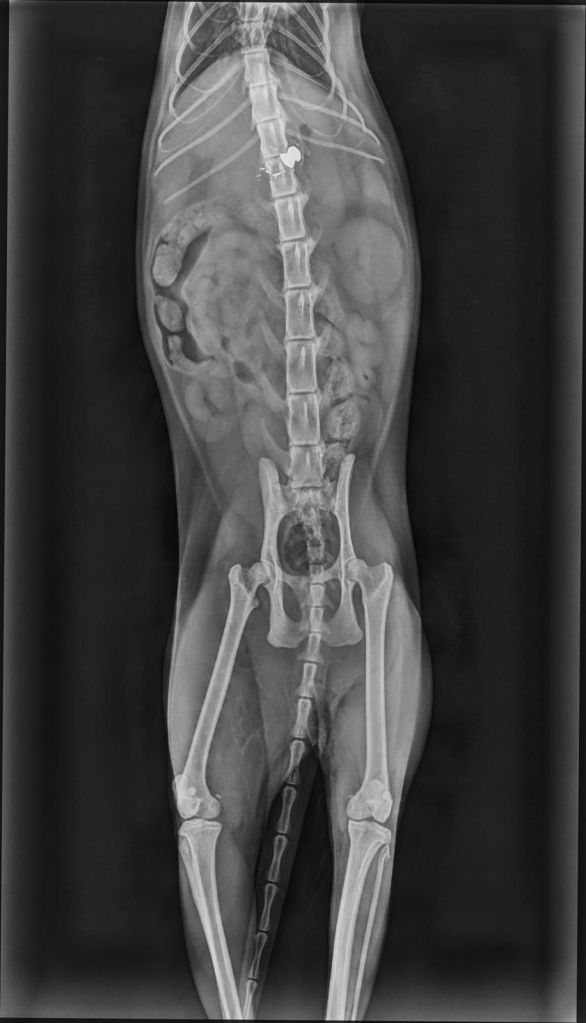

Beschreibung | Man fand Asha regungslos auf der Straße. Sie war unfähig sich zu bewegen und ein beherzter Mann brachte sie zum Tierarzt. Dort wurde sie geröntgt und man stellte fest, dass ein Geschoss in ihrer Wirbelsäule steckte. Es wurde auch noch ein CT gemacht um zu erkennen, ob eine Operation hilfreich wäre. Der Orthopäde befürwortete eine O.P., obwohl er sich nicht sicher war, ob ihr Rückenmark schon zu sehr geschädigt ist, oder ob eine O.P. noch erfolgreich sein könnte. Aber Asha sollte diese Chance bekommen. Es wurde eine Hemilaminektomie durchgeführt, doch während der O.P. stellte man leider fest, dass das Rückenmark zu stark geschädigt war und Asha somit nie wieder wird laufen können. Das war ein großer Schock für alle Beteiligten. Asha ist so eine süße Maus und sie ist sehr traurig, denn leider muss sie derzeit alleine in einer kleinen Box leben. Mit den Vorderbeinchen kann sie sich schon etwas fortbewegen, nur leider sind ihre Vorderbeine zu wenig trainiert, so dass sie sich noch schwer tut. Aber wir wissen es von anderen Fällen, dass sich die Muskulatur prima trainieren lässt und sie sich dann sogar auf das Bett hochkrabbeln oder sich auf den Kratzbaum hochziehen können. Durch ihre Lähmung ist Asha leider inkontinent. D.h. sie hat keine Kontrolle über ihren Schließmuskel und auch nicht über die Blase. Sie hat eine Überlaufblase, die aber dennoch 1x am Tag ausmassiert werden muss. Asha ist so eine liebe Katze. Im ersten Moment ist sie etwas reserviert und zurückhaltend, wenn sie dann aber merkt, dass keine Gefahr besteht, reibt sie ihr Köpfchen an einem und will immerfort gestreichelt werden. Dabei schnurrt sie voller Seligkeit. Sie kann sehr gut mit anderen Katzen zusammenleben. Allerdings darf sie nicht bedrängt werden. Asha könnte sich nicht wehren und das würde sie überfordern. Sie braucht ein ruhiges Zuhause, in dem sie viel Zuneigung und Liebe bekommt. Liebe, schon etwas ruhigere Kinder sind herzlich willkommen. Vor Hunden hat Asha Angst. Es wäre schön, wenn Asha etwas Grün und frische Luft zur Verfügung stehen würden. Eines Tages wird sie ihre Muskulatur an den Vorderbeine gut trainiert haben und kann dann durch die Wohnung flitzen. Da wären auch draußen etwas Rasen und frische Luft super Asha wird FIV und Leukose getestet, Tollwut, Schnupfen, Seuche und Leukose geimpft, entwurmt, gechipt und kastriert abgegeben. |